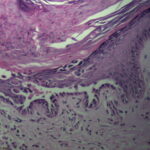

The characteristic changes in Darier’s disease include the following: (a) a peculiar form of dyskeratosis resulting in the formation of corps ronds and grains; (b) suprabasal acantholysis leading to the formation of suprabasal clefts or lacunae; and (c) irregular upward proliferation into the lacunae of papillae lined with a single layer of basal cells, so-called villi (Fig. 6-27). There are also papillomatosis, acanthosis, and hyperkeratosis. The dermis shows a chronic inflammatory infiltrate. In some cases, there is downward proliferation of epidermal cells into the dermis.

The corps ronds occur in the upper stratum malpighii, particularly in the granular and horny layers; grains are found in the horny layer and as acantholytic cells within the lacunae. Corps ronds possess a central homogeneous, basophilic,

pyknotic nucleus that is surrounded by a clear halo. By virtue of size and the conspicuous halo, corps ronds stand out clearly . Peripheral to the halo lies basophilic dyskeratotic material as a shell . The nonstaining halo in some instances is partially replaced by homogeneous, eosinophilic dyskeratotic material . Compared with the corps ronds, the grains are much less conspicuous. They resemble parakeratotic cells but are somewhat larger. The nuclei of grains are elongated and often grain shaped and are surrounded by homogeneous dyskeratotic material that usually stains basophilic but may stain eosinophilic. The lacunae represent small, slitlike intraepidermal vesicles most commonly located directly above the basal layer. They contain acantholytic cells and show premature partial keratinization. Because of shrinkage, some of them are elongated, and these then appear identical with the grains in the horny layer. The villi projecting into the lacunae may be quite tortuous, so on histologic examination, some of them appear in cross section as rounded dermal structures lined by a solitary row of basal cells .